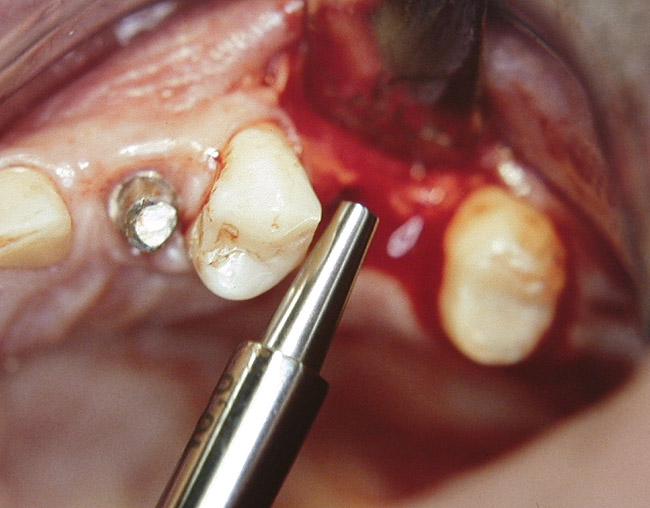

At the time of surgery, the tooth was extracted without harvesting any mucosal flap because the implant site was prepared by means of a pilot drill bur (Figure 13) and alternating osteotomes (Figure 14A and Figure 14B). The implant was positioned and showed primary stability. The implant was loaded 2 days after surgery. Then, splinted PFM crowns supported by custom gold abutments were delivered. At 6 months posttreatment, the radiograph revealed no bone resorption and the clinical result was optimal (Figure 15A and Figure 15B).

Figure 14a  Alternating osteotomes were used to prepare the implant site.

Figure 14a

Figure 14b  Alternating osteotomes were used to prepare the implant site.

Figure 14b